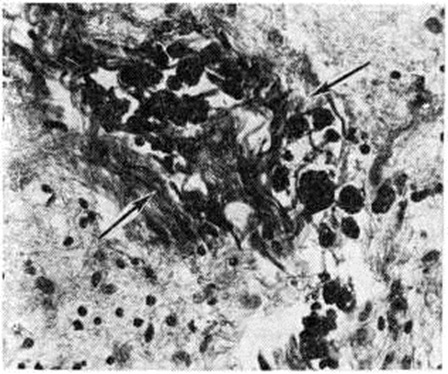

Микропрепарат ткани головного мозга с глиомезодермальным рубцом (указан стрелками), содержащим зерна гемосидерина (обозначены черным цветом), после небольшого кровоизлияния (окраска по Ван Гизону; × 200).